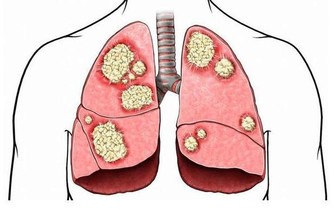

4、腫瘤

當女性盆腔中的生殖器發生腫瘤,如子宮肌瘤、宮頸癌、卵巢癌、卵巢囊腫等,同樣會壓迫神經系統,出現腰痛現象。